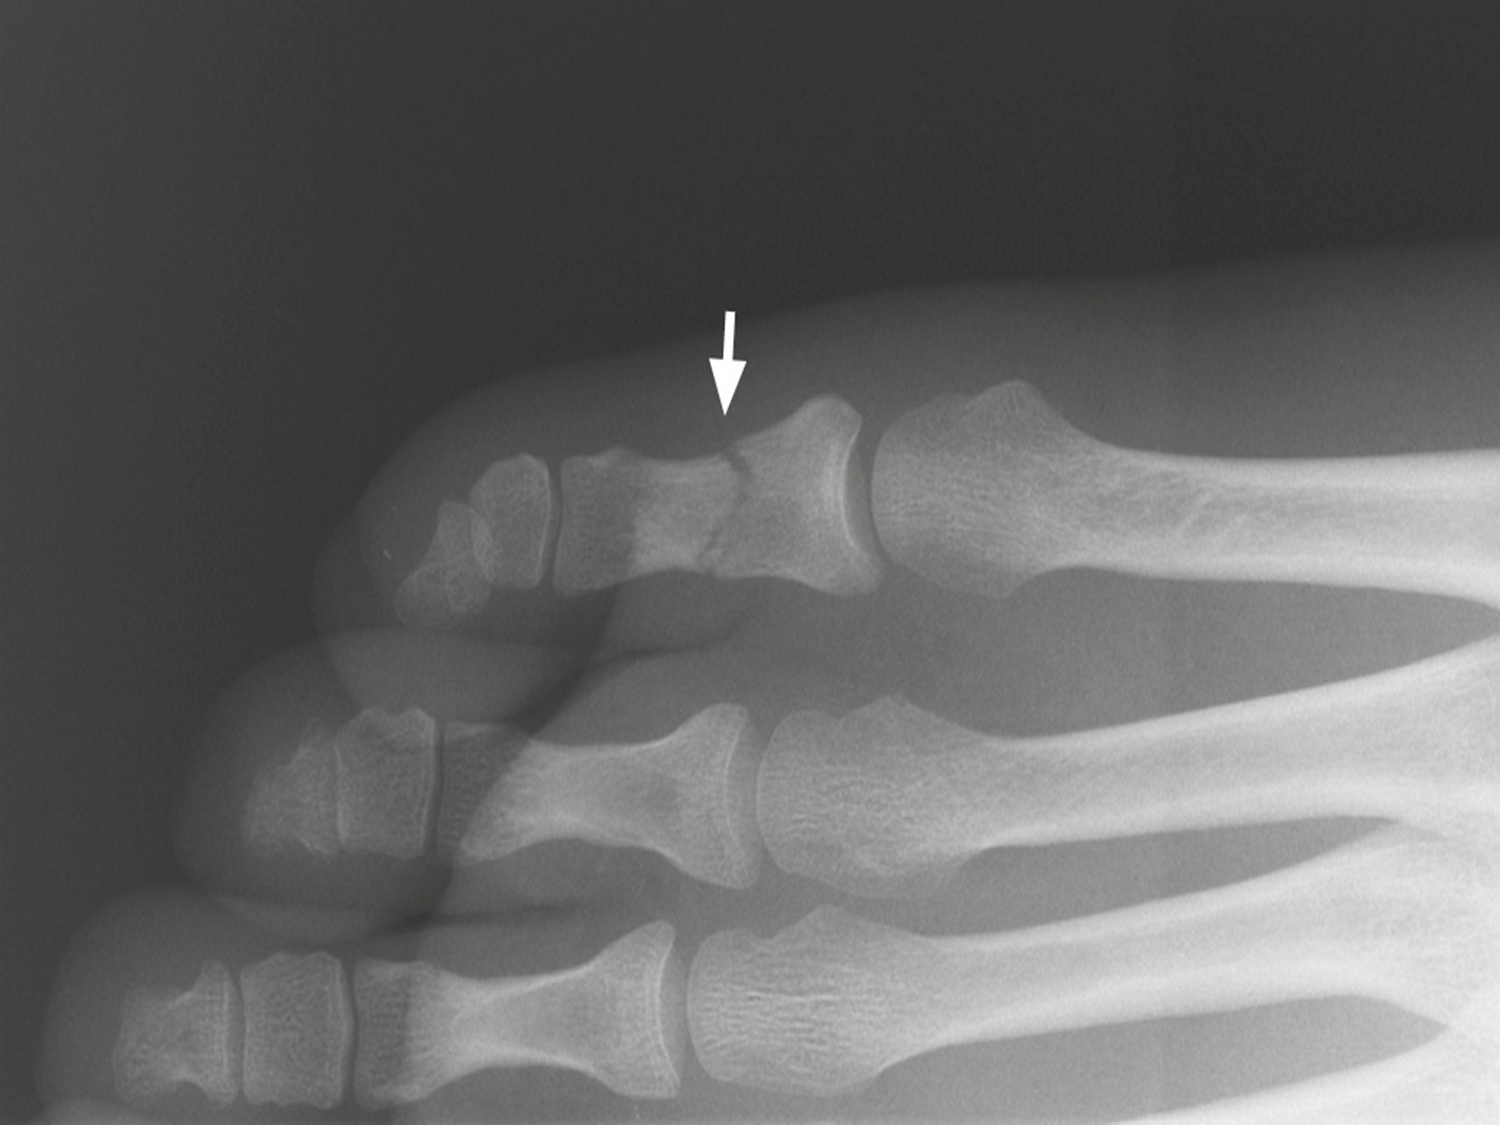

arthritis

inflammation of joints. -can cause narrow joint space -bone erosions -bone spurs

cartilage on the long bones prevent bones from rubbing against each other